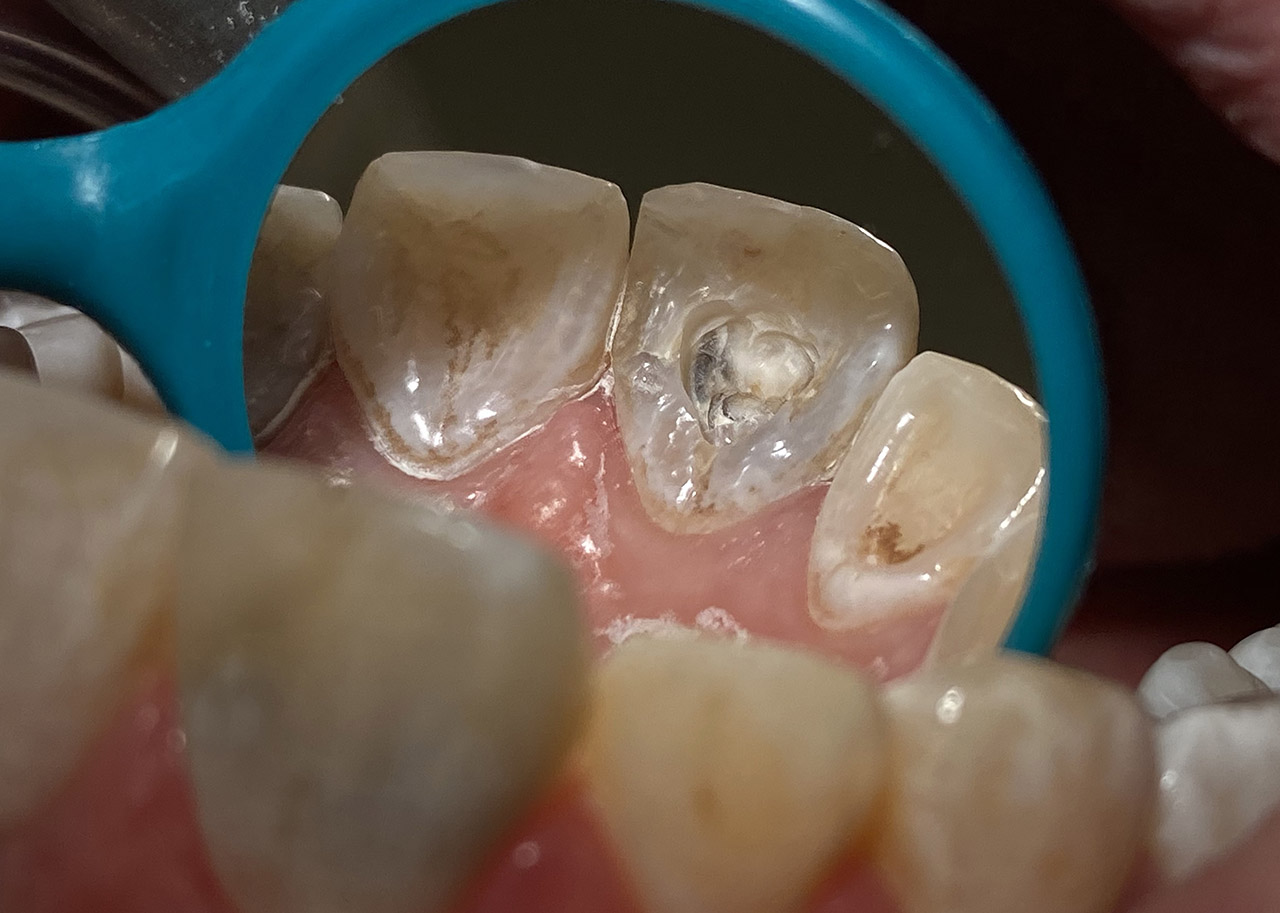

Wurzelbehandlung/Endodontie:

Massiver Paro-/Endodefekt bei den Zähnen 38&37. Extraktion von 38 (Weisheitszahn) und Wurzelbehandlung von 37 (4 Kanäle). Defekt vollständig ausgeheilt.